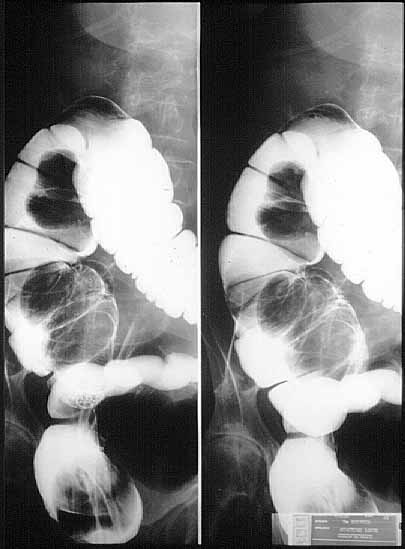

fig. 1

Figura 1. Enema opaco: masa intraluminal en colon ascendente que provoca una invaginación ileocecal